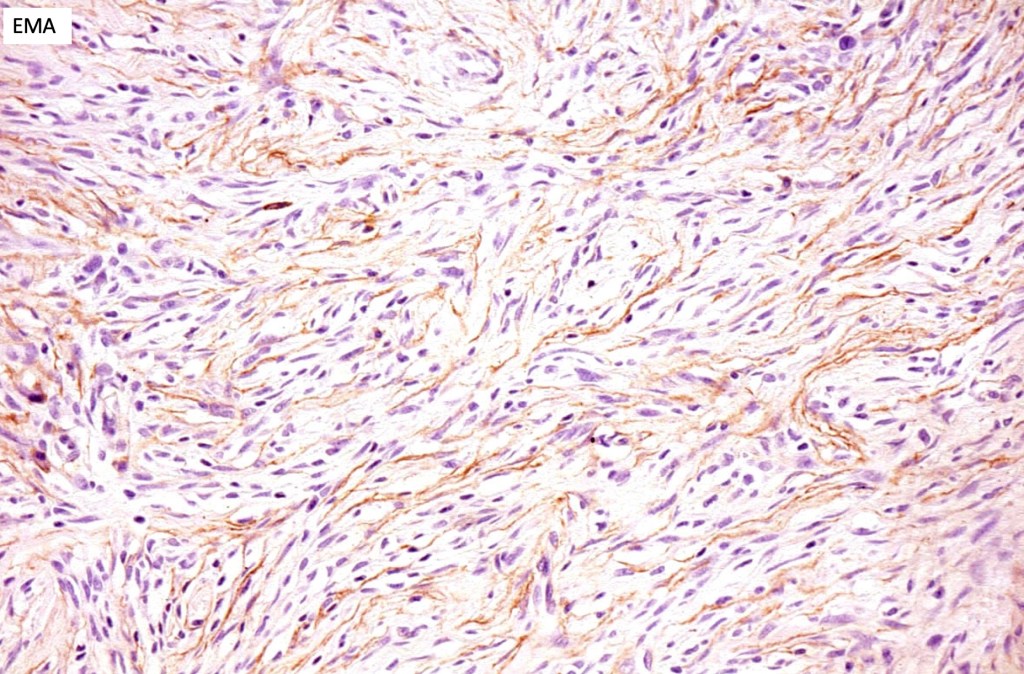

Neurocristic hamartoma

This is exceedinly rare and represents a hamartomatous lesion of neural crest origin The scalp is most often affected but although it can also present on the face, neck, buttock and elsewhere. It presents as folliculocentric brown or blue/black papules and nodules sometimes associated with alopecia. Exceptionally melanoma supervenes.

Histologically it presents in varying proprtions of banal and blue nevus accompanied by scattered dendritic cells associated with neurofibroma-like spindle cells and Schwann cell nodules with Meissner corpusces surrounded by sustentacular EMA positive cells. The lesion typically ensheathes the hair follicles.